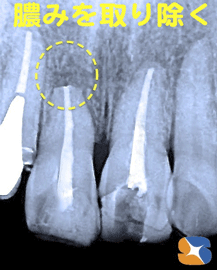

グラグラ止まらず 手術して膿みを除去

コラム「グラグラ止まらず 手術して膿みを除去」の画像